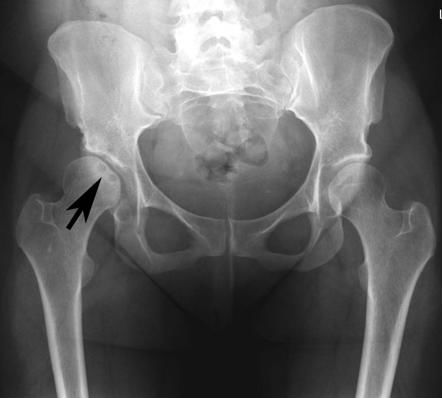

- Рентгенография тазобедренных сочленений. Этот метод исследование дает возможность специалистам при длительном течении патологии определить участки некроза головки бедренной кости.

Рентгенограмма при асептическом некрозе бедренной кости

Рентгенография.

На рентгенограммах зона АН головки бедренной кости определяется, как правило, при достаточной длительности заболевания. На ранних стадиях заболевания при рентгенологическом исследовании патологических изменений кости может не определяться, не смотря на то, что пациента могут уже беспокоить выраженные боли в суставе. На поздних стадиях АН присоединяется остеоартроз, и бывает трудно определить какая из этих болезней обусловливает в большей степени отмечающиеся у пациента симптомы.